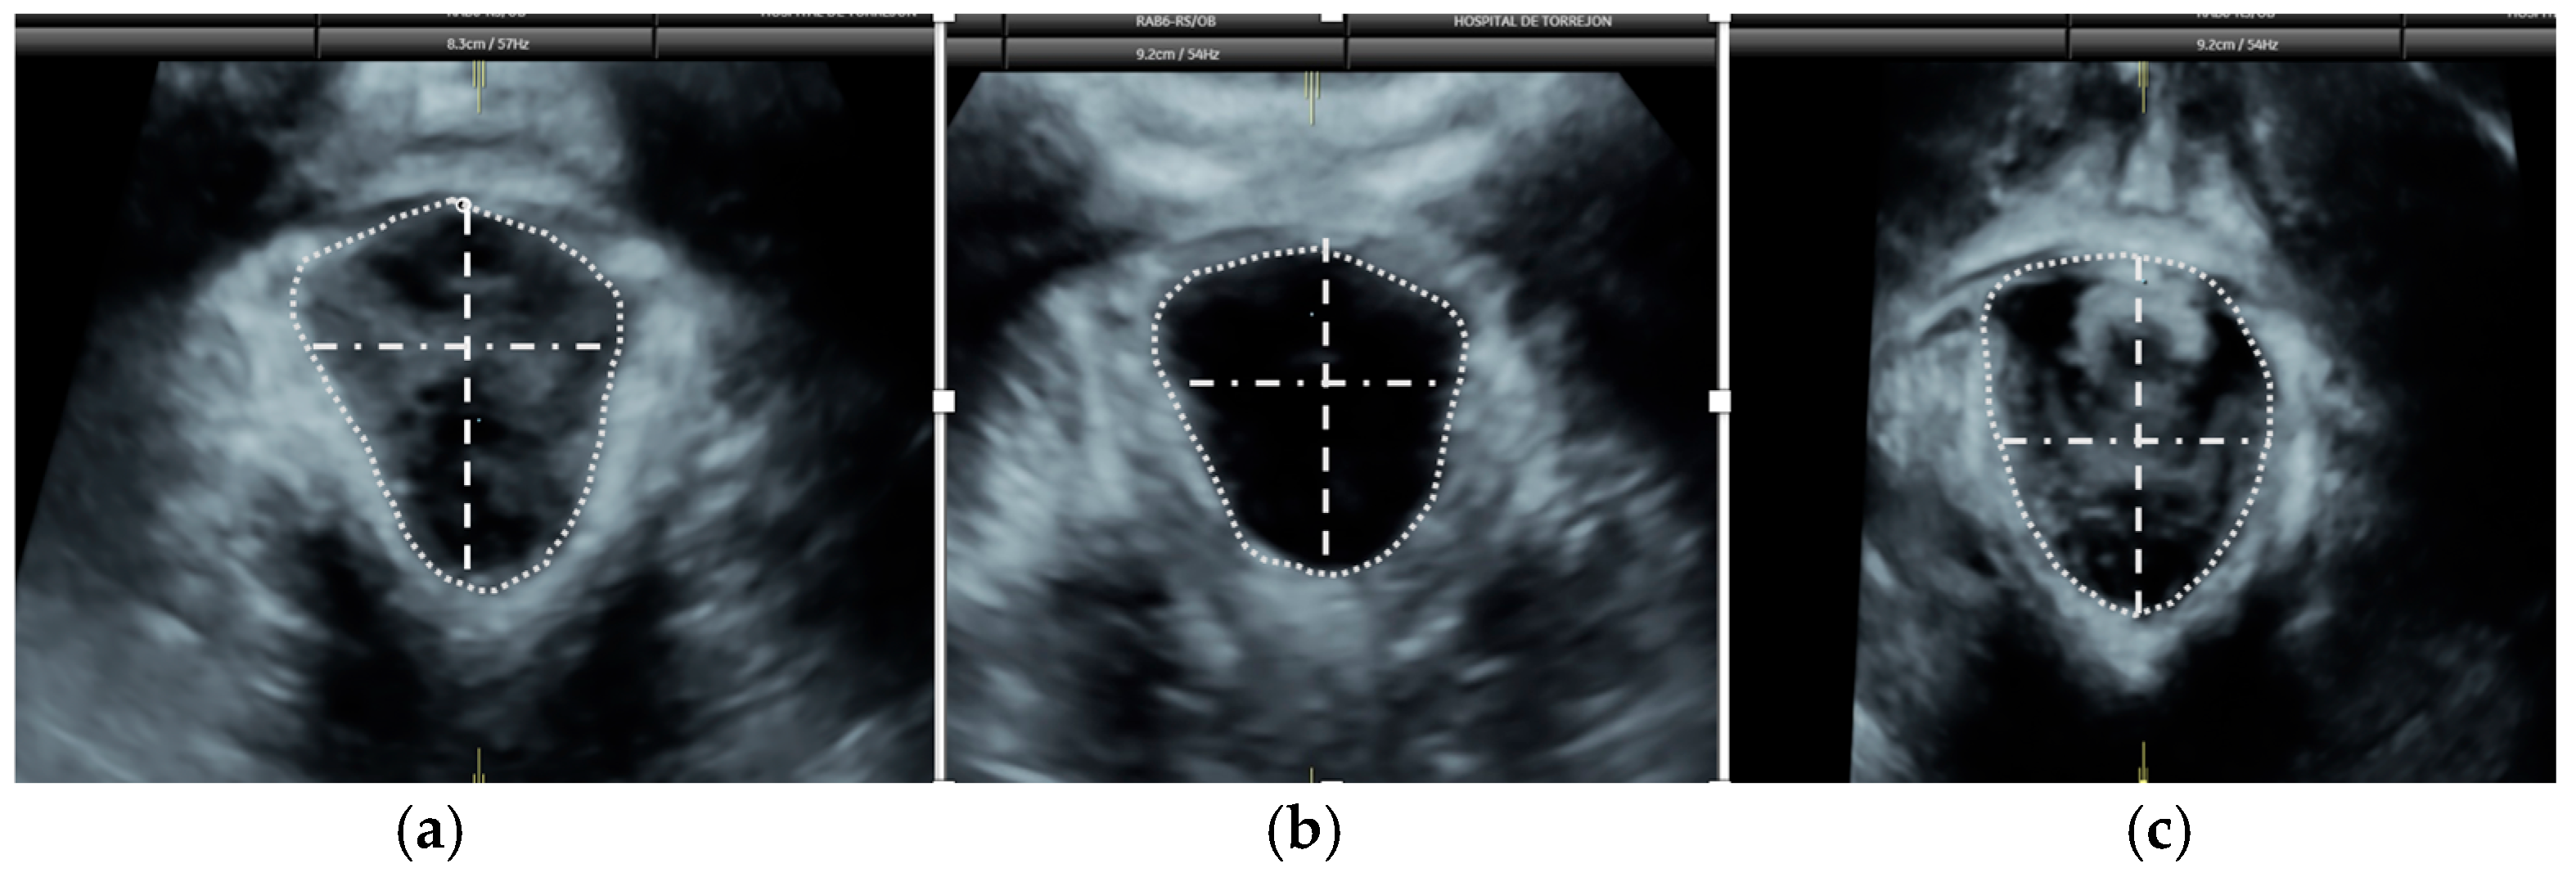

2.6. Pelvic Floor Ultrasound

- Dietz, H.P.; Shek, K.L. Tomographic ultrasound imaging of the pelvic floor: Which levels matter most? Ultrasound Obstet. Gynecol. 2009, 33, 698–703. [Google Scholar] [CrossRef] [PubMed]